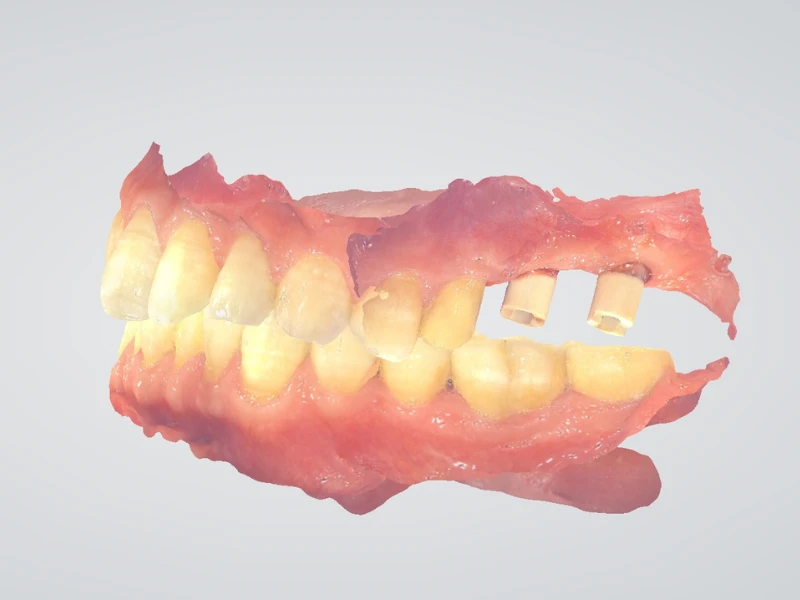

MÚI CHỊU

Múi răng khớp vào rãnh của răng đối diện được gọi là múi chịu. Múi trong của răng trên và múi ngoài của răng dưới được gọi là múi chịu.

MÚI CẮT

Múi ngoài của răng trên và múi trong của răng dưới được sử dụng để cắt thức ăn và được gọi là múi cắt.